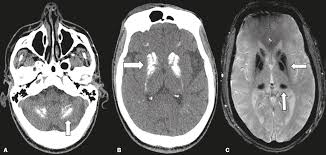

Calcificações intracranianas neonatais e diagnóstico diferencial com infecções congênitas (pseudo-TORCH)